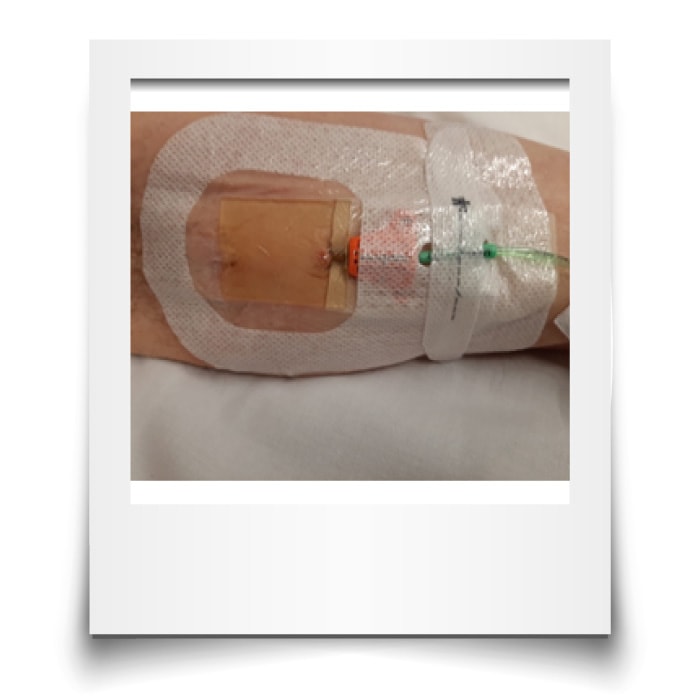

8. Uso de sistema de fijación sin suturas + cianoacrilato + membrana transparente:

Todas las guías internacionales desaconsejan el uso de suturas para la fijación de los catéteres vasculares. La evidencia ha demostrado que las suturas incurren en mayor riesgo de punción accidental del profesional, de mayor riesgo de trombosis y de infección, además de ser incómodas para el paciente, sobre todo, en algunas zonas anatómicas.

Los sistemas de fijación sin suturas pueden ser adhesivos o subcutáneos, siendo estos últimos indicados en pacientes cuyo catéter vaya a permanecer más de 3 semanas o en casos de piel delicada o MARSI, con riesgo de salida accidental o en pacientes no colaboradores (desorientados, niños, neonatos) (imagen 8)

El uso del cianoacrilato en el punto de inserción ayuda a la hemostasia y controla el eventual sangrado post inserción, haciendo que la primera cura pueda realizarse a la semana, en vez de en las primeras 24 horas. Así mismo, el cianoacrilalto funciona como una barrera estéril protectora del punto de inserción durante el tiempo que esté presente.

Para finalizar, el uso de la membrana transparente semipermeable permite una observación directa del punto de inserción y una cobertura efectiva de toda la piel que lo rodea. Es recomendable elegir aquellas membranas con mayor transpirabilidad para el vapor de la piel, de modo que éste no se acumule bajo el apósito y pueda crear maceración cutánea.